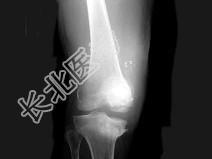

- 单项选择题男,67岁, 脊髓痨患者,右下肢麻木, 右膝关节肿胀,结合图像, 最可能的诊断是 ( )

A、创伤性关节炎

B、退行性骨关节病

C、神经性关节病

D、风湿性关节炎

E、痛风